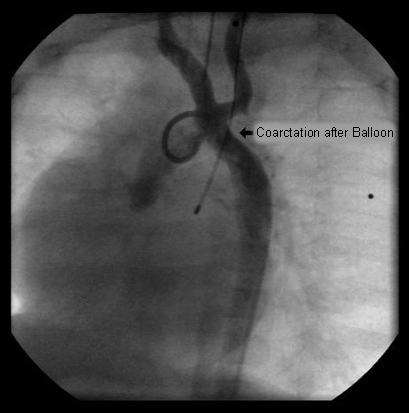

Balloon angioplasty of the narrowed region leads to complete resolution of the obstruction

From the personal collection of Jeffrey Gossett, MD, Children's Memorial Hospital, Northwestern University, Chicago; used with permission